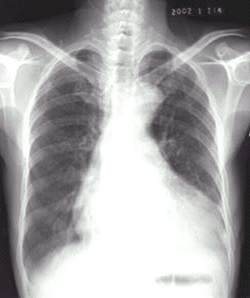

03卷-4.病史:女性,73岁,血压升高10年,心悸、头晕、乏力2周。诊断(本题满分2.00分)

本题答案:B

题目解析:【该题针对“X线-心脏增大(二尖瓣型、主动脉型和普大型)”知识点进行考核】